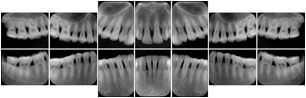

Table OO.1.1-1 shows structured display standard templates, where Viewset ID is based on the Japanese Society for Oral and Maxillofacial Radiology (JSOMR) classification provided by JIRA (Japan Medical Imaging and Radiological Systems Industries Association, www.jira-net.or.jp). Expected or typical teeth to be imaged location, region and designation codes are based on ISO 3950-2010, Dentistry - Designation system for teeth and areas of the oral cavity. For all the hanging protocols listed in OO.1.1-1, the value to use for Hanging Protocol Creator (0072,0008) is "JSOMR" and the value to use for Hanging Protocol Name (0072,0002) does not include "JSOMR" (e.g., "DL-S001A", not "JSOMR DL-S001A").